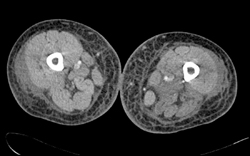

Post Open Reduction Internal Fixation (ORIF)